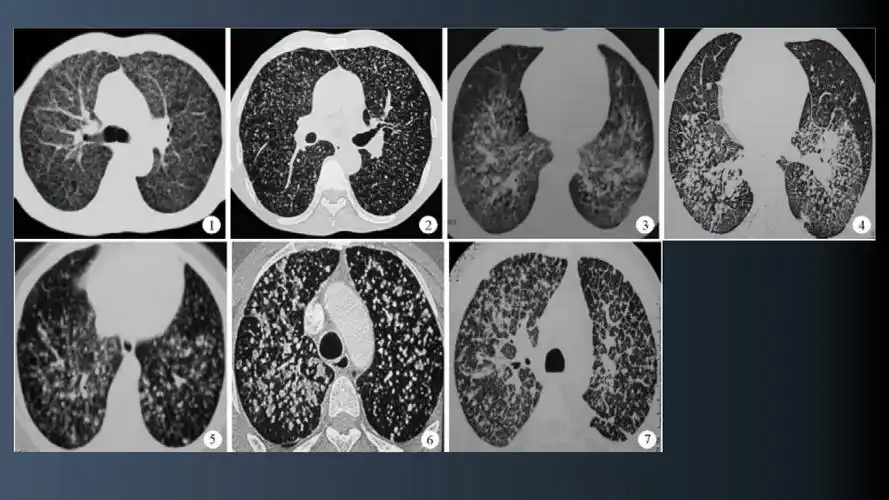

肺结核与尘肺鉴别诊断ppt课件.ppt